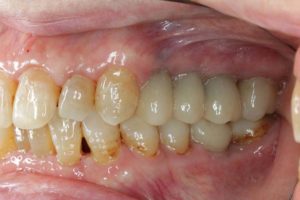

院長のコメント

長い間お疲れ様でした。この患者さんは、奥歯を何本も失っていて満足なお食事ができない状態でした。前歯も所々虫歯で黒ずんでいて気になって口を開けて笑えないとおっしゃっていました。そもそも、最初はお嬢様の結婚の前までに綺麗にしたいというものだったのですが、治療をしていくうちに奥歯の大切さを実感していただいたようです。

さて、この方は奥歯にインプラントを入れたのですが、あまり骨がなく普通の手術ではインプラント入れらません。そのため、インプラント手術だけならほとんど痛みはないのですが、上顎洞挙上術という難易度の高い手術を併用したため、手術後に痛みや腫れが若干出たようです。

奥歯にインプラントを入れ、前歯はホワイトニングやダイレクトボンディング、セラミックなどで修復しました。